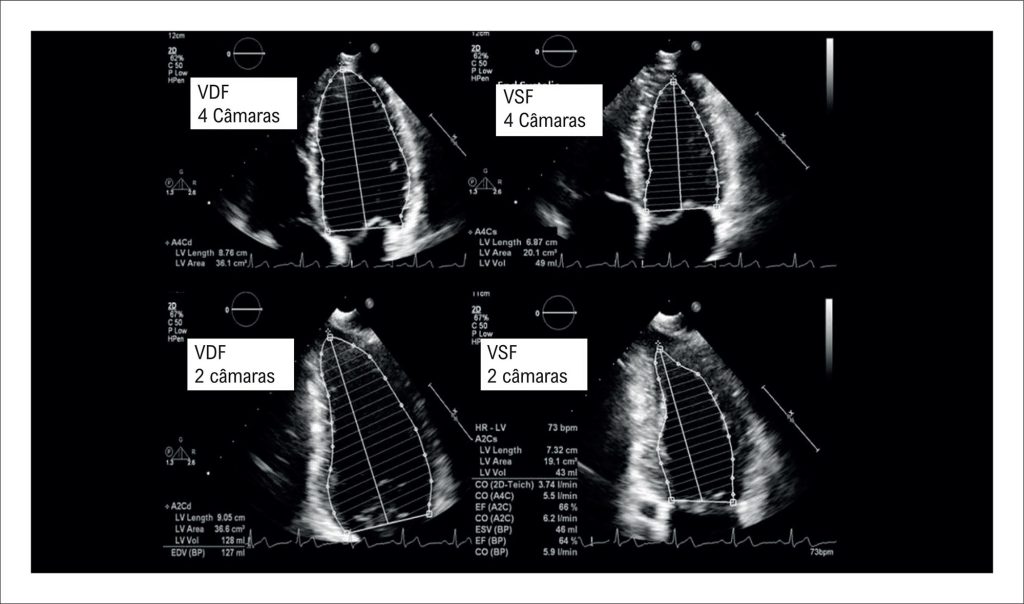

A avaliação da função sistólica do ventrículo esquerdo pelo ecocardiograma é essencial na prática clínica e na pesquisa cardiovascular. Embora a fração de ejeção do ventrículo esquerdo continue sendo o parâmetro mais utilizado, os avanços nas técnicas ecocardiográficas ampliaram a avaliação diagnóstica. Esta revisão resume os principais métodos para a avaliação da função sistólica, desde medidas lineares tradicionais até abordagens volumétricas bidimensionais e tridimensionais mais modernas. São discutidos os papéis e as limitações do método de Simpson, da ecocardiografia com contraste, imagem tridimensional, análise da deformação miocárdica e das ferramentas de inteligência artificial, enfatizando a importância de uma abordagem integrada e individualizada.